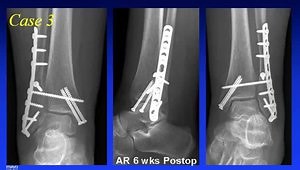

Case Discussion: Treatment of Distal Tibia Fractures

A video from Richard Claridge (as part of The Event 2013), posted on Jan 24, 2014.